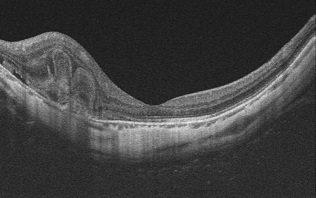

・診断: 加齢黄斑変性に類似していますが、強度近視による眼底の特徴や光干渉断層計(OCT)画像における特徴を慎重に見極めることで診断可能です。黄斑部の眼底に出血があっても脈絡膜新生血管がない場合(単純出血)もあり得ますので、光干渉断層血管撮影(OCTA)で脈絡膜新生血管の有無を調べます。

※上記症例に抗VEGF薬注射を行って2カ月目の眼底写真とOCT画像。